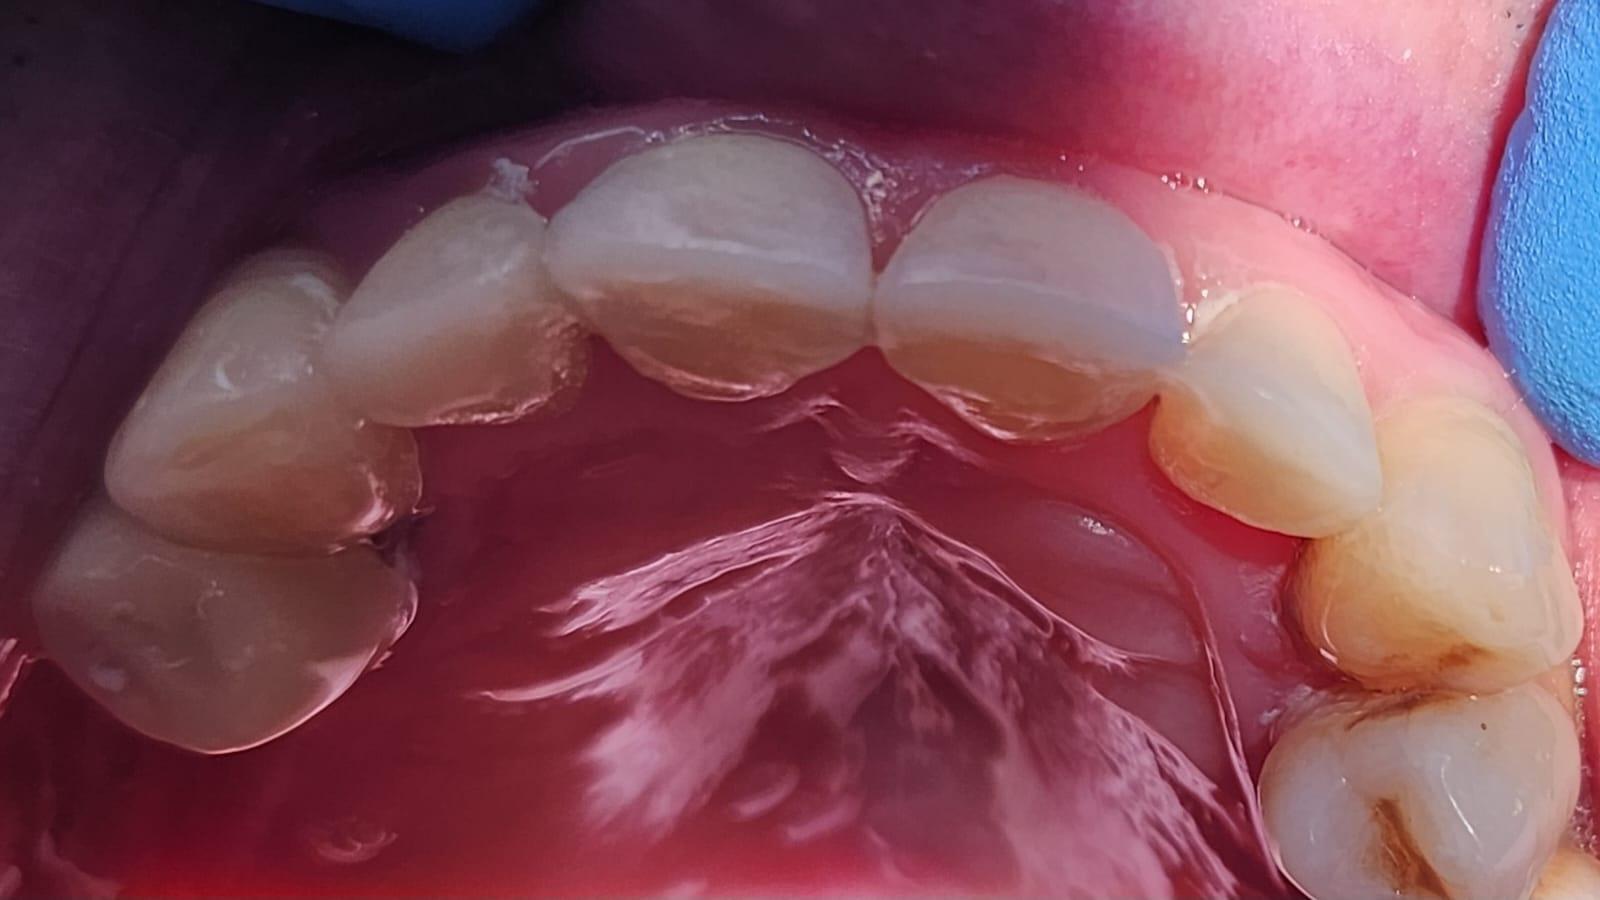

Clinica LUY ESTHETIC ART defineste parodontoza ca fiind rezultatul direct al placii dentare, care se depune pe suprafata dintilor, dar si in apropiere de marginea gingivala. Aceasta boala duce la pierderea dintilor, chiar daca ei sunt aparent sanatosi si nu prezinta carii. Edentatiile, afecteaza vorbirea, aspectul, dar si capacitatea de a mesteca.

Semnele aparitiei paradontozei:

– gingiile sangereaza la periaj;

– gingii rosii si inflamate;

– mobilitatea sau deplasarea dintilor;

– retractii gingivale cu expunerea radacinilor dentare;

– halena.